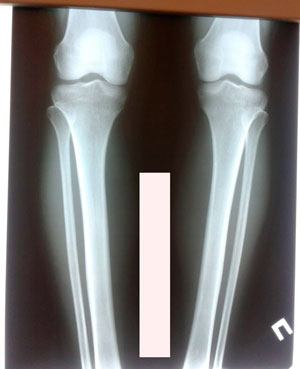

Исходник - 34 года. Южная Корея.

Дата операции - 18.11.2019.

Вложения

IMG_7175-18-11-19-07-55.JPG

IMG_7171-18-11-19-07-55.JPG